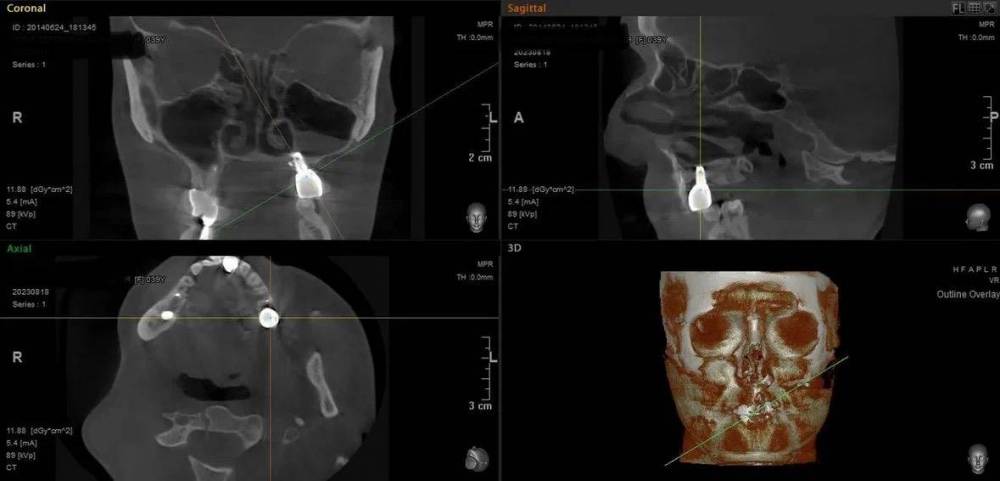

Mitt Опубликовано 29 октября, 2023 Поделиться Опубликовано 29 октября, 2023 (изменено) Здравствуйте. Ж., 39 лет. Так получилось, что мне нужно решить, что делать с имплантатом на месте верхней шестерки. А тк я не обладаю необходимой компетенцией, очень нуждаюсь в подсказках специалистов. Дано: 1. 2014-2015 гг - удаление зуба, синус лифтинг, имплантация с пластикой мягких тканей, установка коронки. 2. 2015 - 2019 гг - проблема контактов с рядом находящимися пятым и седьмым зубами, воспаление десны вокруг 5, имплантант, 7. Решалось путем композитных «накладок» на 5 и 7 зубы. 3. 2019 - 2023 гг - пластика мягких тканей, удаление 7 зуба с подсыпкой графта, еще штуки 3 или 4 пластики, включая вестибулопластику, временная коронка. 4. 2023 г - установка новой постоянной коронки, 5 месяцев тишины, с августа гной в районе имплантата (десна спокойна). Проблемы общие для всех временных периодов - тандем с пазухой и периодические ближе к постоянным боли разной интенсивности и локации (пазуха, 7 зуб, место от 7 зуба, стенка носа, кость), мне сложно лоцировать( Мне нужно выбрать, что делать дальше: попробовать почистить имплантат, или уже отпустить=удалить. Вариант почистить и еще сделать пластику пока не рассматриваю, тк после стольких пластик частичная парастезия неба. Может быть, кто-то подскажет, к какому решению в итоге прийти.. P.s. Я не знаю , какие скрины кт нужны( кт 08.2023 Изменено 29 октября, 2023 пользователем Mitt Ссылка на комментарий